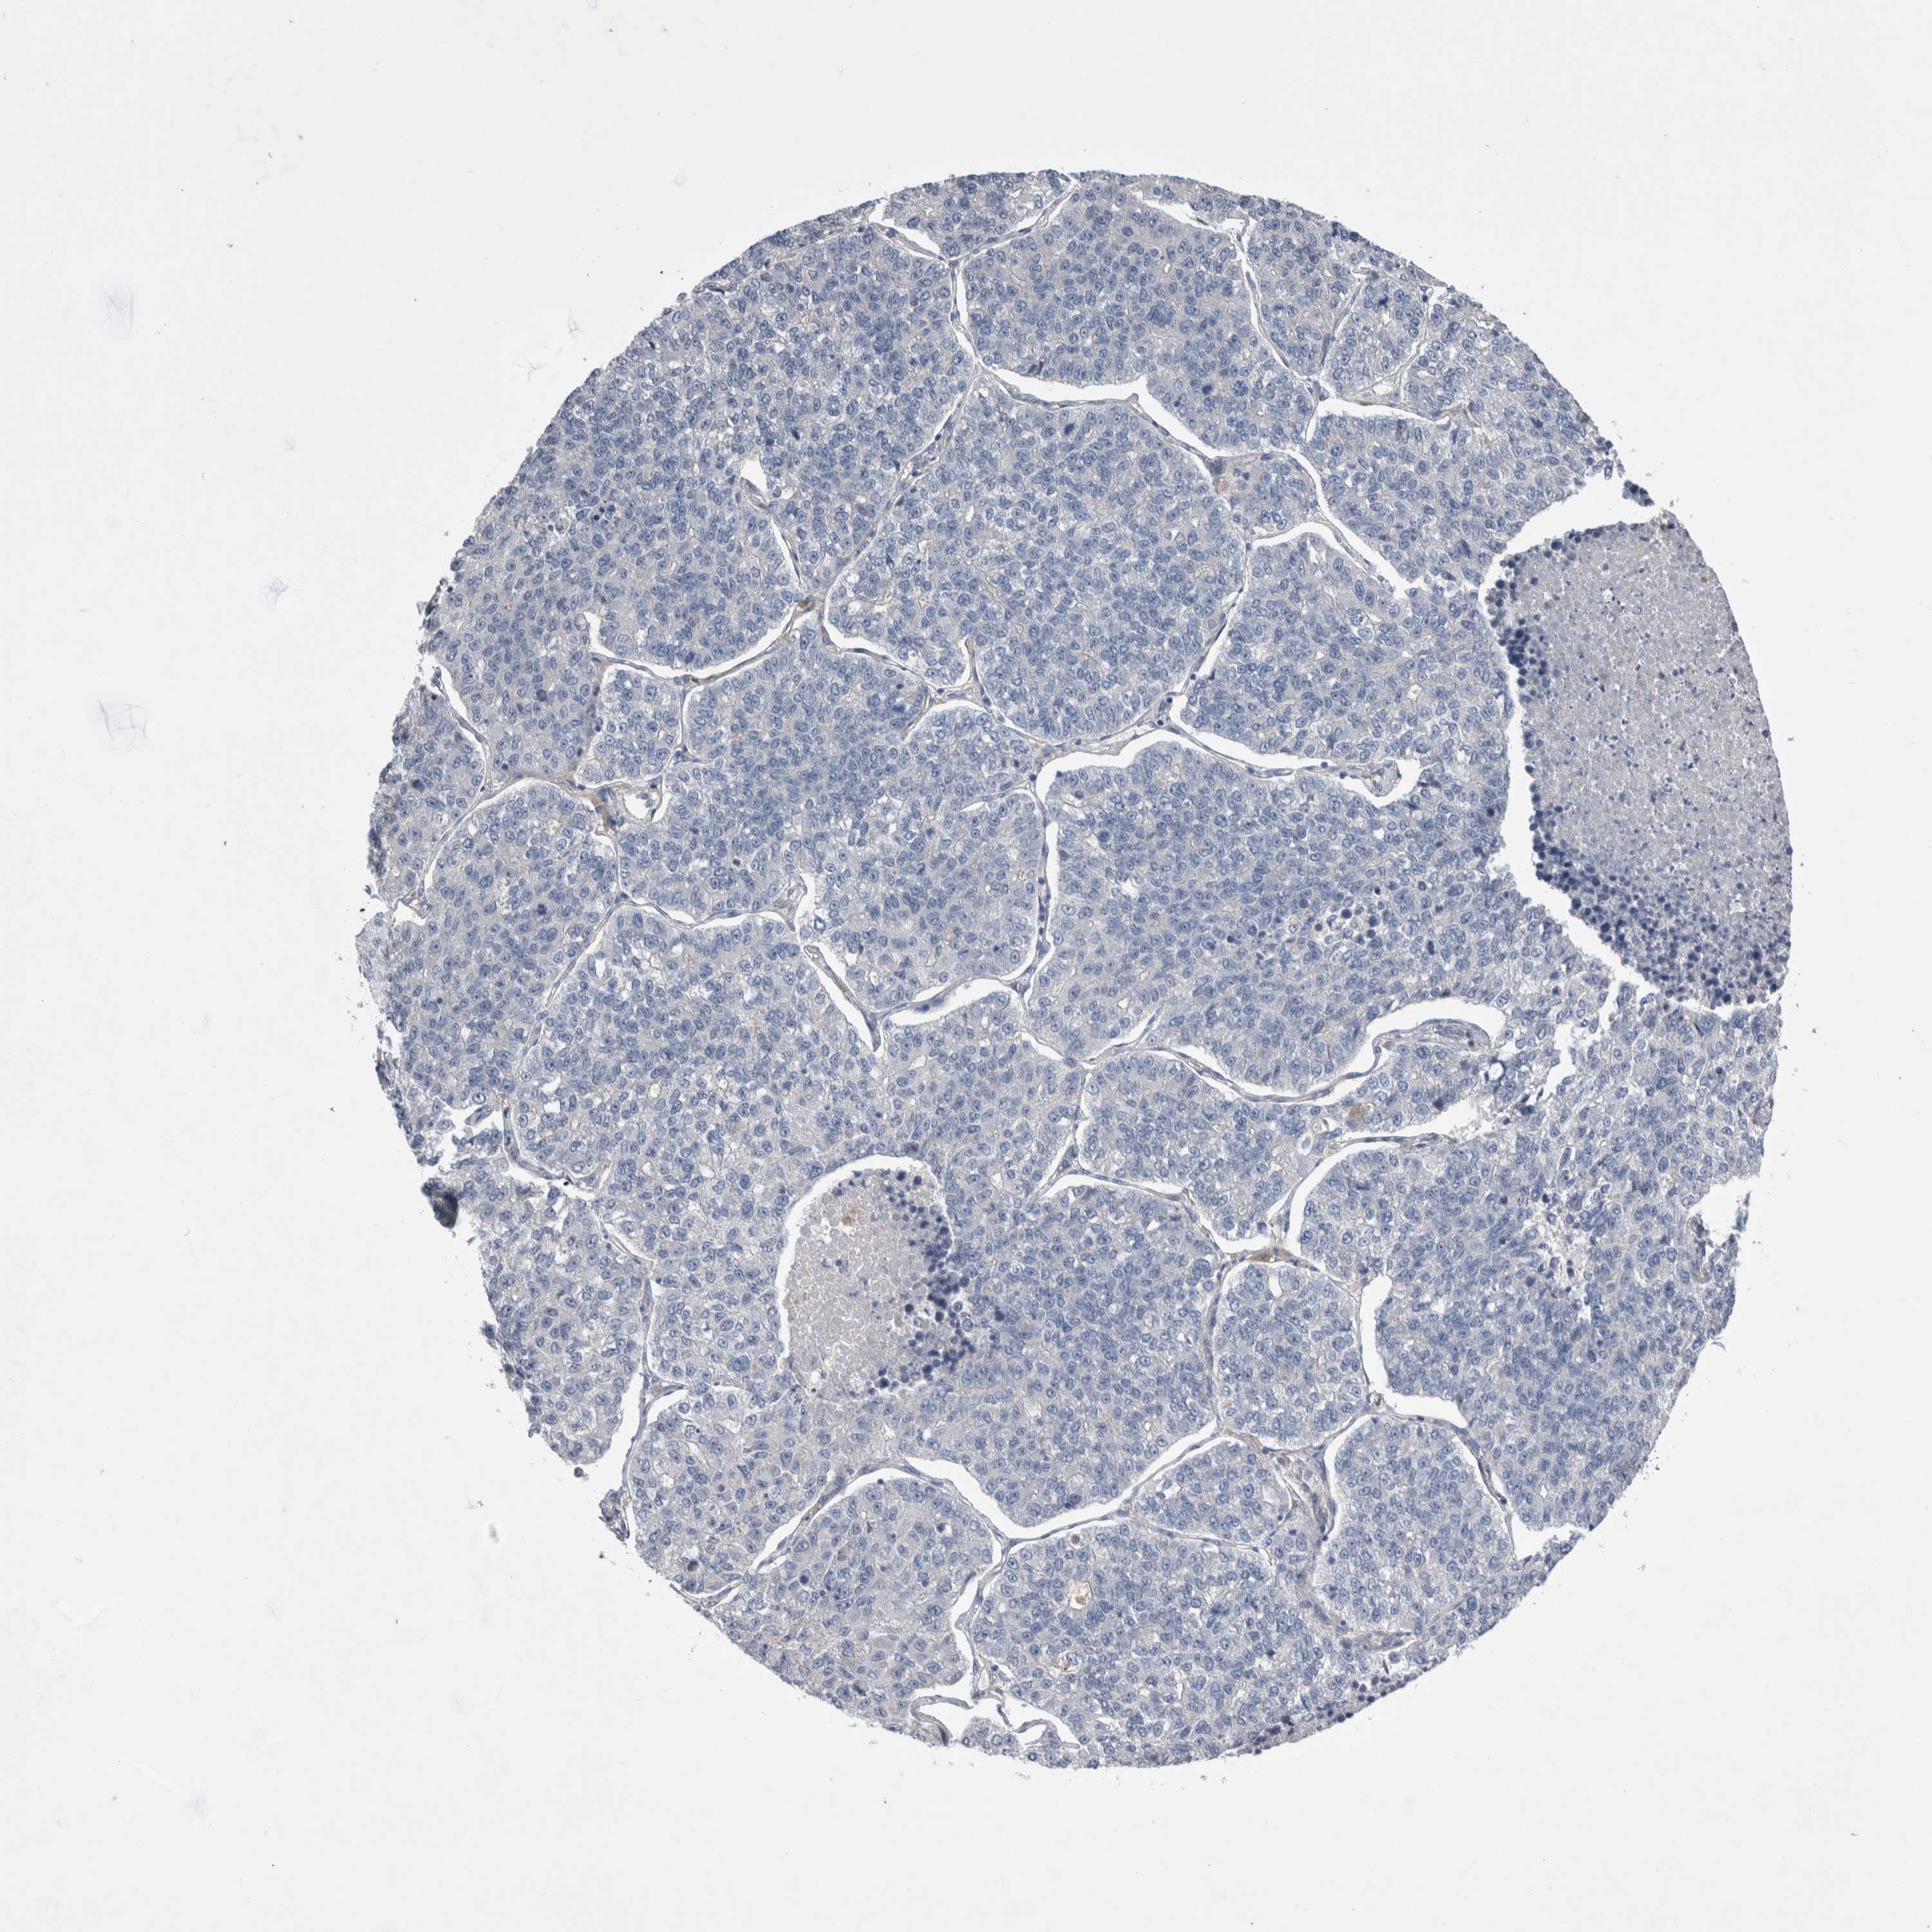

CANCER LUNG CANCER Show tissue menu